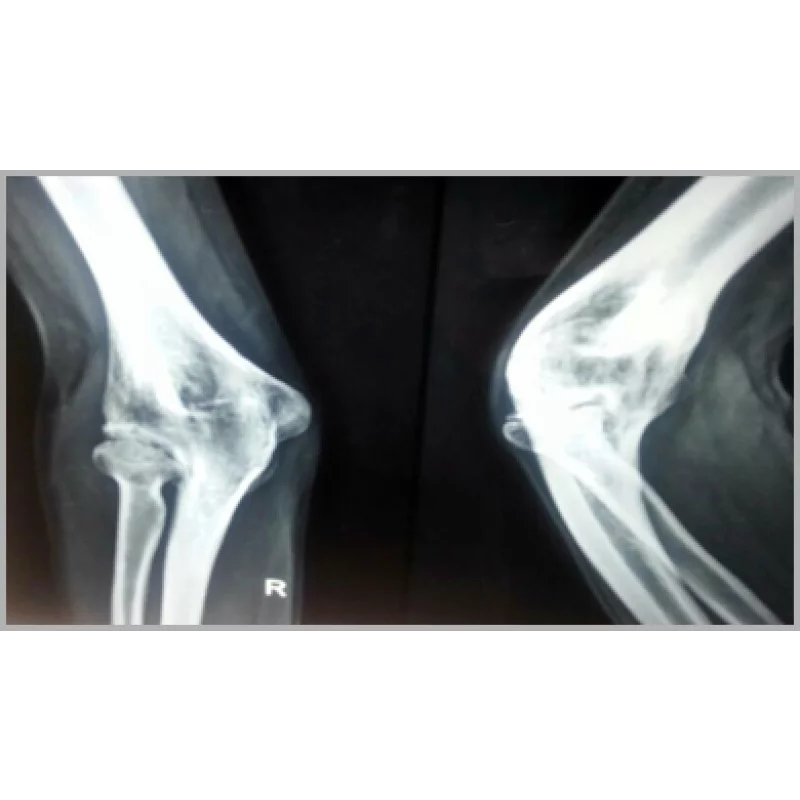

Fused Elbow

A Young Male Aged 36 Years Had History Septic Elbow In Childhood And Was Operated For The Same In Childhood. He Had Fused Elbow After That And Had No Movement Of That Elbow Which Was Fixed In About 70 Degrees Of Flexion And No Supination And Pronation . He Was Operated After Proper Investigations And Underwent Total Elbow Replacement. Only In Three Weeks Had Good Improvement In Elbow Movement Which Was 20 Degrees Of Flexion To 100 Degrees.... Read more